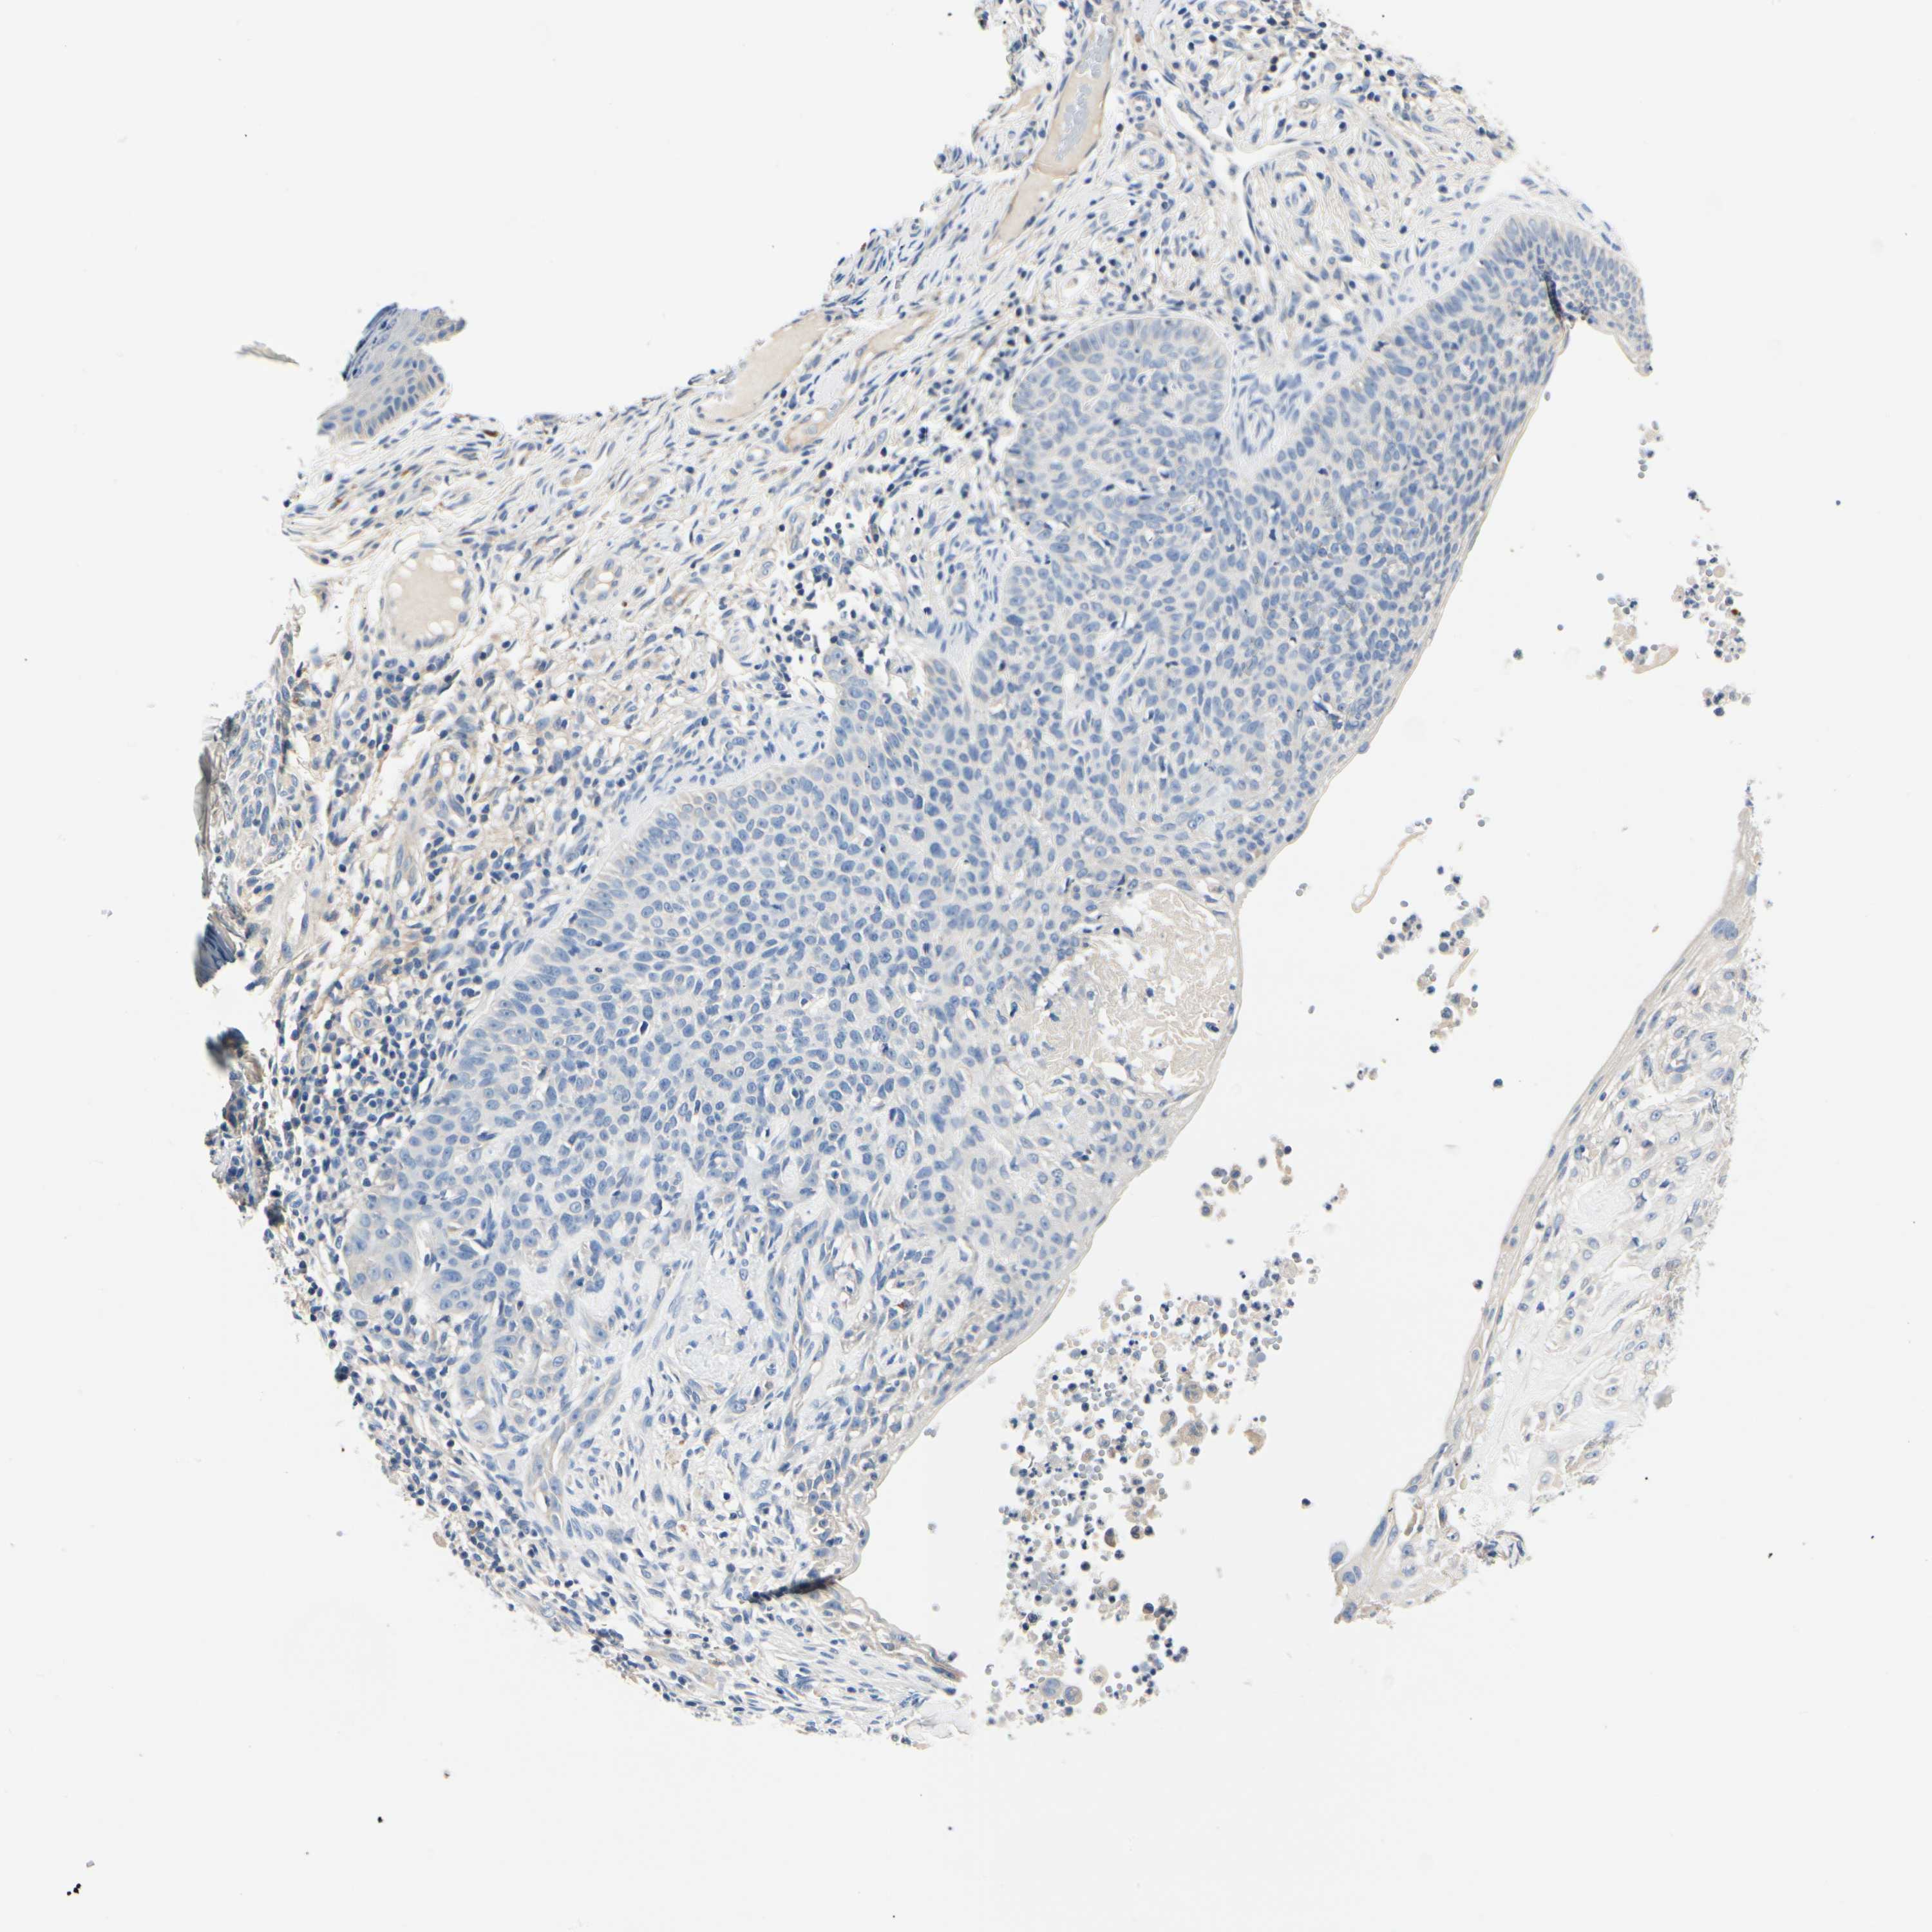

SKIN CANCER - Protein expressioni

A mouse-over function shows sample information and annotation data. Click on an image to view it in a full screen mode. Samples can be filtered based on level of antibody staining by selecting one or several of the following categories: high, medium, low and not detected. The assay and annotation is described here.

Antibody stainingi

Antibody staining in the annotated cell types in the current human tissue is reported as not detected, low, medium, or high, based on conventional immunohistochemistry profiling in selected tissues. This score is based on the combination of the staining intensity and fraction of stained cells.

Each image is clickable and will lead to virtual microscopy that enables deeper exploration of all samples and also displays staining intensity scores, fraction scores and subcellular localization as well as patient and tissue information for each sample.

Antibody HPA008257

Squamous cell carcinoma, NOS